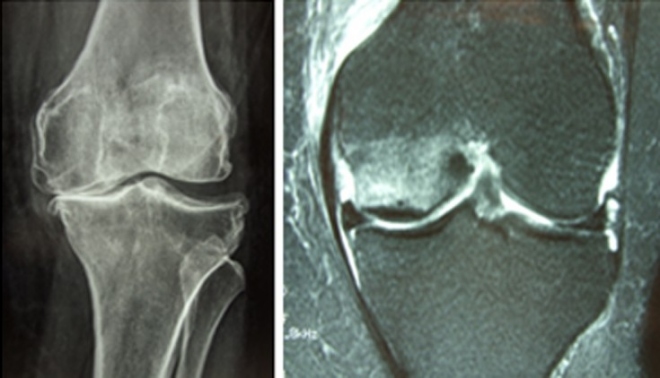

Οι διάφορες φάσεις της αρθρίτιδας έχουν διαφορετική απεικόνιση στην ακτινογραφία και στην μαγνητική τομογραφία. Στην ακτινογραφία διακρίνεται η λέπτυνση του χόνδρου, η παραμόρφωση του άξονα, η σκλήρυνση του οστού και τα οστεόφυτα.

Στη μαγνητική τομογραφία εμφαίνονται οι βλάβες στους μηνίσκους (ρήξη ή εκφύλιση) των χιαστών συνδέσμων η ελάττωση του πάχους του χόνδρου, η νέκρωση του χόνδρου και η νέκρωση των υποκειμένων οστών.